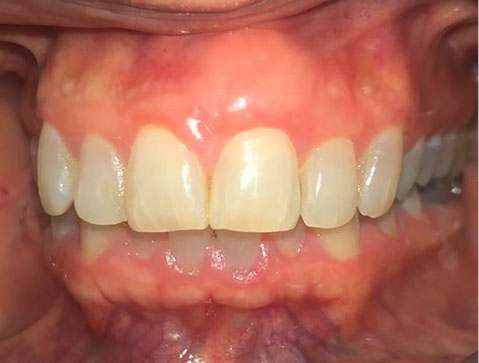

In our case, after placing the graft, the defect resulting from the excisional biopsy was fully reconstructed. The patient was satisfied with the esthetic appearance and without any inflammation or bleeding on probing after six months of follow-up (Figure 6).

japid-12-95-g006

Figure 6. Follow-up after 6 month.